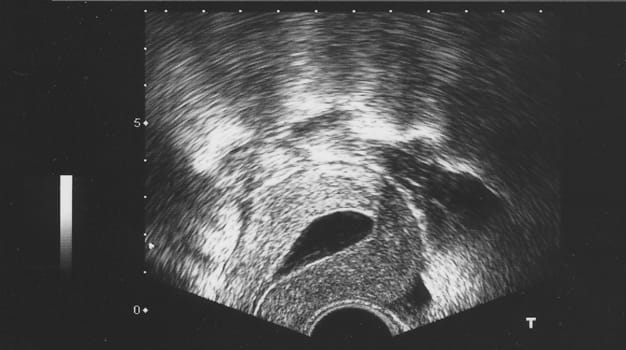

We use saline ultrasound to assess the endometrial cavity of your uterus. A thin, soft catheter is passed through the cervix into the uterus, and a small amount of sterile saline solution is gently instilled. A transvaginal ultrasound is used to confirm the absence of polyps, scarring, or fibroids inside the uterus.

This ultrasound image shows a normal endometrial cavity. Polyps and fibroids (myomas) would show as lighter shade “filling defects” within the dark saline-filled endometrial cavity.